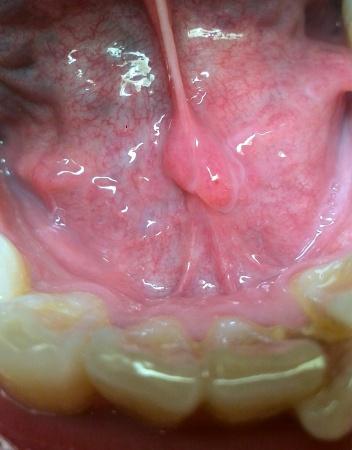

口腔正常组织还是囊肿?

口腔正常组织还是囊肿? 左面舌体上是什么?

应该是正常组织吧。

同问,谢谢!是不是正常组织?